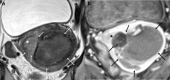

Although rare, uterine sarcoma is a diagnosis that no one wants to miss. Often benign leiomyomas (fibroids) and uterine sarcomas can be differentiated due to the typical low T2 signal intensity contents and well-defined appearances of benign leiomyomas compared to the suspicious appearances of sarcomas presenting as large uterine masses with irregular outlines and intermediate T2 signal intensity together with possible features of secondary spread. The problem is when these benign lesions are atypical causing suspicious imaging features. This article provides a review of the current literature on imaging features of atypical fibroids and uterine sarcomas with an aide-memoire BET1T2ER Check! to help identify key features more suggestive of a uterine sarcoma.